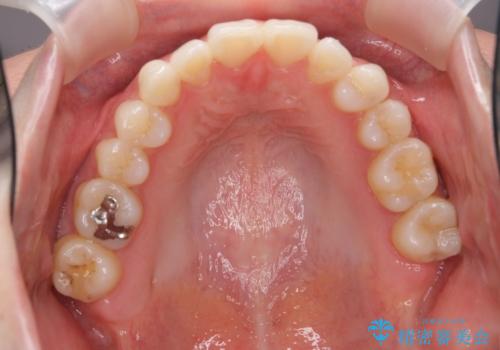

30代女性 前歯のがたつき